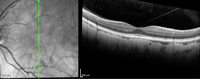

Figura 5. Liberación de la tracción tras la cirugía de vitrectomía.

Figura 6. Adhesión vitreomacular.

Figura 7. Tracción vitreomacular.